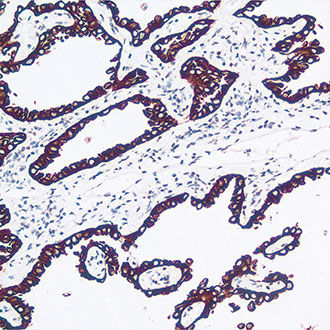

CK5&6

CK5&6 -